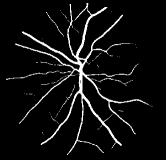

As pointed out in recent works [15, 17], a good semantic segmentation network should learn multi-level features. Further, it should have multiple stages with different receptive fields to learn more inherent features from different scales. FCN, taken as an example, uses skip connections to fuse multiple stages outputs, as well as the HED network, in which a series of side-output layers are added after each stage in VGGNet. The HED network was first proposed for edge detection, and further used for image-level vessel segmentation in recent studies [6, 16], with significant performance. However, our experimental results show that such network architecture is not appropriate for vessel segmentation directly. Figure 1 provides such an illustration. Reasons for this phenomenon are straightforward. On one hand, the side-output of the first layer often contains too many noises. On the other hand, the features produced by the last side-output layer are too coarse due to information loss of pooling operation. Obviously, the inaccurate vessel map of side-output1 and side-output4 should have negative impacts on the final segmentation result.

2.2 Bottom-top short connections

With the deepening of DSN network, the receptive field of each side-output layer gets larger, which makes the corresponding vessel map much blurrier as observed from the first row in Figure 1, especially for side-output4. These observations inspired us to pass low level fine semantic information to high levels to alleviate the blurring situation.

Bottom-top short connections aim to refine high-level segmentation results. However, we can observe from the first two rows in Figure 1 that the vessel map generated by the first side-output layer contains too many noises while the map generated by the last side-output could capture the main vessel structure. Therefore, we propose delivering high-level structural information to the first side-output layer to reduce its noises. We implemented this kind of information delivery by a top-bottom short connection from conv4 to feat_conv1, which can been seen in Figure 4. We first convolved the last convolution of conv4 using 1 convolution kernels with size 33. Then the obtained feature map are up-sampled 8 to get feat_4_1. The information (feat_4_1) passed from conv4 are concatenated with feat_conv1 to form feat_conv1_fuse (see Figure 5). At last, one hand hand, we perform a 11 convolution operation on feat_conv1_fuse to get the information (feat_1_2) delivered to feat_conv2. On the other hand, we performed convolution operation with a kernel size of 11 and sigmoid transformation for feat_conv1_fuse sequentially to obtain the segmentation result (side 1). At last, side 1 is compared with the ground truth to get the loss of the first side-output layer.

In addition, we can observe from Figure 1 that the side-output1 and side-output4 of the BTS-DSN were more accurate compared with those of the DSN.